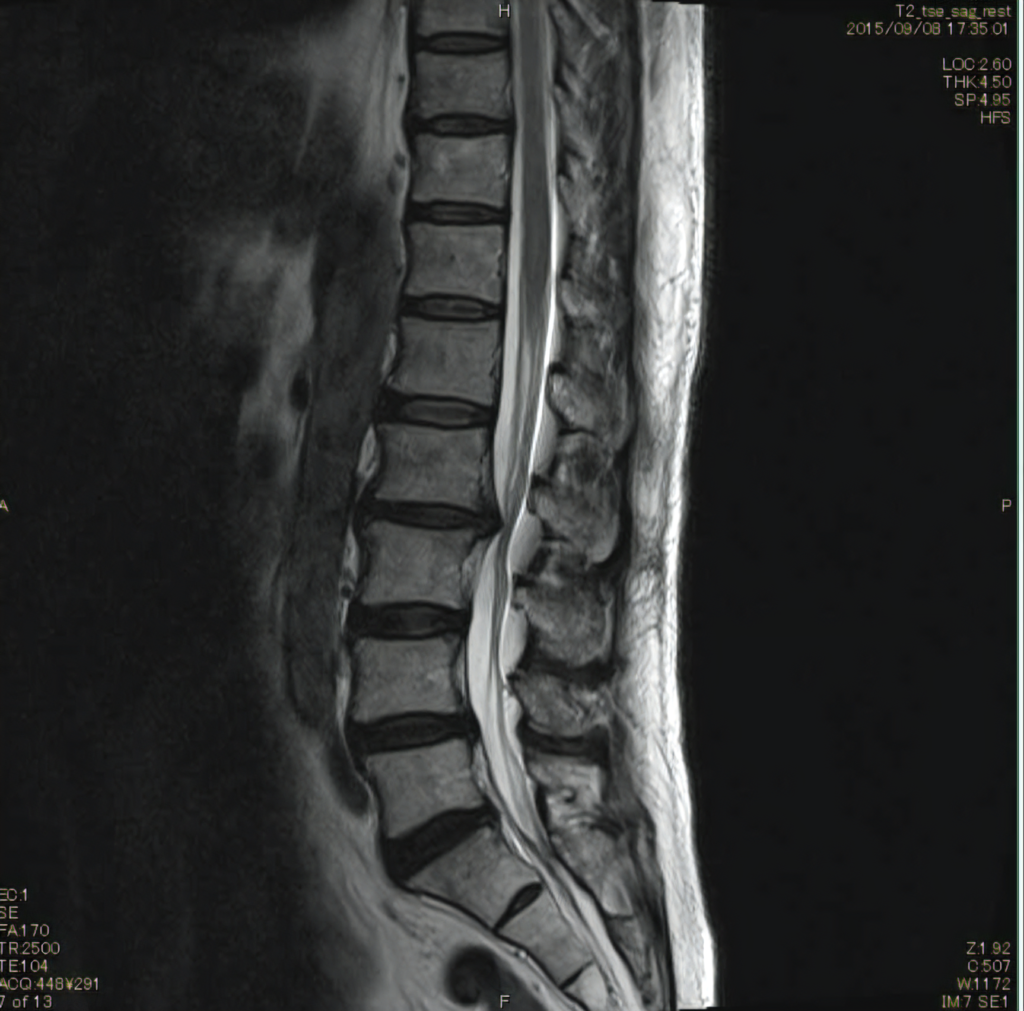

レントゲンでは腰椎4番のすべり症が確認されるものの、MRI画像ではすべりの補正作用が強く、またゴルフを好んでされていたため、腰椎の2番が椎間板で神経を圧迫していました。

2015年撮影MRI 椎間板の突出が鋭角に飛び出しているのがわかる。

2018年撮影MRI 突出が丸みを帯び減少がみられる。この頃には症状の7〜8割が消失。

初めの2週間は4番のすべりがあるので、5番の矯正を行いすべりの安定化を促しました。この時点では症状の改善は見られません。2週間を経過した頃から腰椎2番の矯正を行いました。また、患者様には半年はゴルフは控えるようにお願いしました。施術開始から約1か月経過したあたりから、症状が半減しました。最初はカイロプラクティックの施術に懐疑的であった患者さまも、このあたりから完全に信用してくださるようになりました。そして半年後には、症状の70%が消失し、本当に喜んでいただきました。施術と同時に体感トレーニングも指導させていただき、6年経過した現在は、ゴルフもコンペでご一緒させていただくほど回復されました。